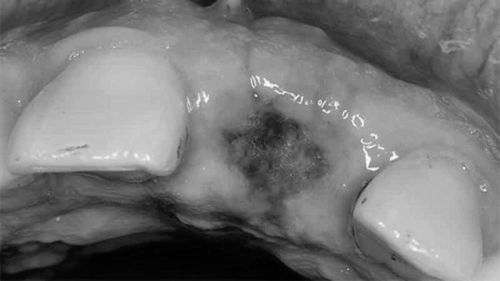

Виникнення «сухий лунки»

Це ще один вид ускладнень. У групі ризику знаходяться жінки, що приймають протизаплідні таблетки і засоби, завзяті курці і люди похилого віку. Ознаками недуги можна вважати відсутність на ранці кров'яного згустку. Він не утворюється через добу, як це зазвичай буває, крім того, через 3-4 дні хворий починає скаржитися на появу тупий, ниючий біль.

Якщо ще й голий шматок кістки, загоєння просувається вкрай повільно. Біль може стати інтенсивної, тому варто негайно звернутися до лікаря.

Самостійне лікування «сухий лунки» може привести до додаткових ускладнень

Розрізнити ознаки недуги можна і за зовнішнім виглядом ранки. Кость часто оголена, немає ні згустку, ні крові. Як правило, пацієнти відразу ж звертаються за допомогою, так як навіть зовнішні ознаки волають у них серйозну тривогу.

Проте, не слід забувати, що лікування проводить тільки лікар, самостійно з проблемою впоратися буде складно і самолікування може призвести до додаткових ускладнень.

Необхідно накладення спеціальної пов'язки, процедура проводиться в клініці. Пов'язка просякнута спеціальними лікарськими препаратами, міняти її також потрібно за допомогою медичних працівників.